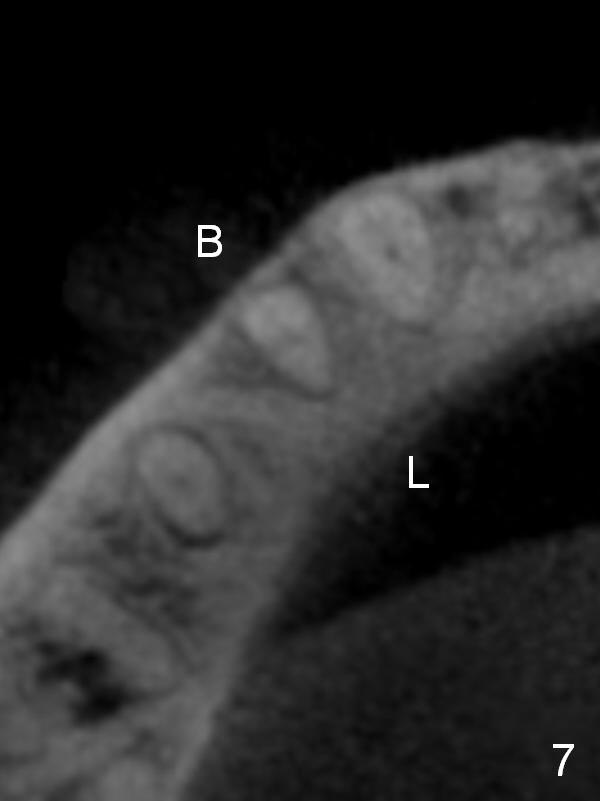

CT sagittal section shows that it is possible to place 4.5x20 mm implant (Fig.6). Axial (Fig.7) and coronal (Fig.9) sections show that the lingual (L) plate is much thicker than the buccal (B) one. To prevent the implant being buccally deviated, a Lindermann bur is used after extraction (black area in Fig.8,10) to remove ~ 1mm bone from the lingual plate (red area in Fig.8,11). A 2 mm pilot drill is placed as lingual as possible (green in Fig.8,11). If the implant (Fig.12) starts to deviate buccally while being placed, remove it from the osteotomy and remove more bone from the lingual plate. Place the implant again and monitor the trajectory tightly.